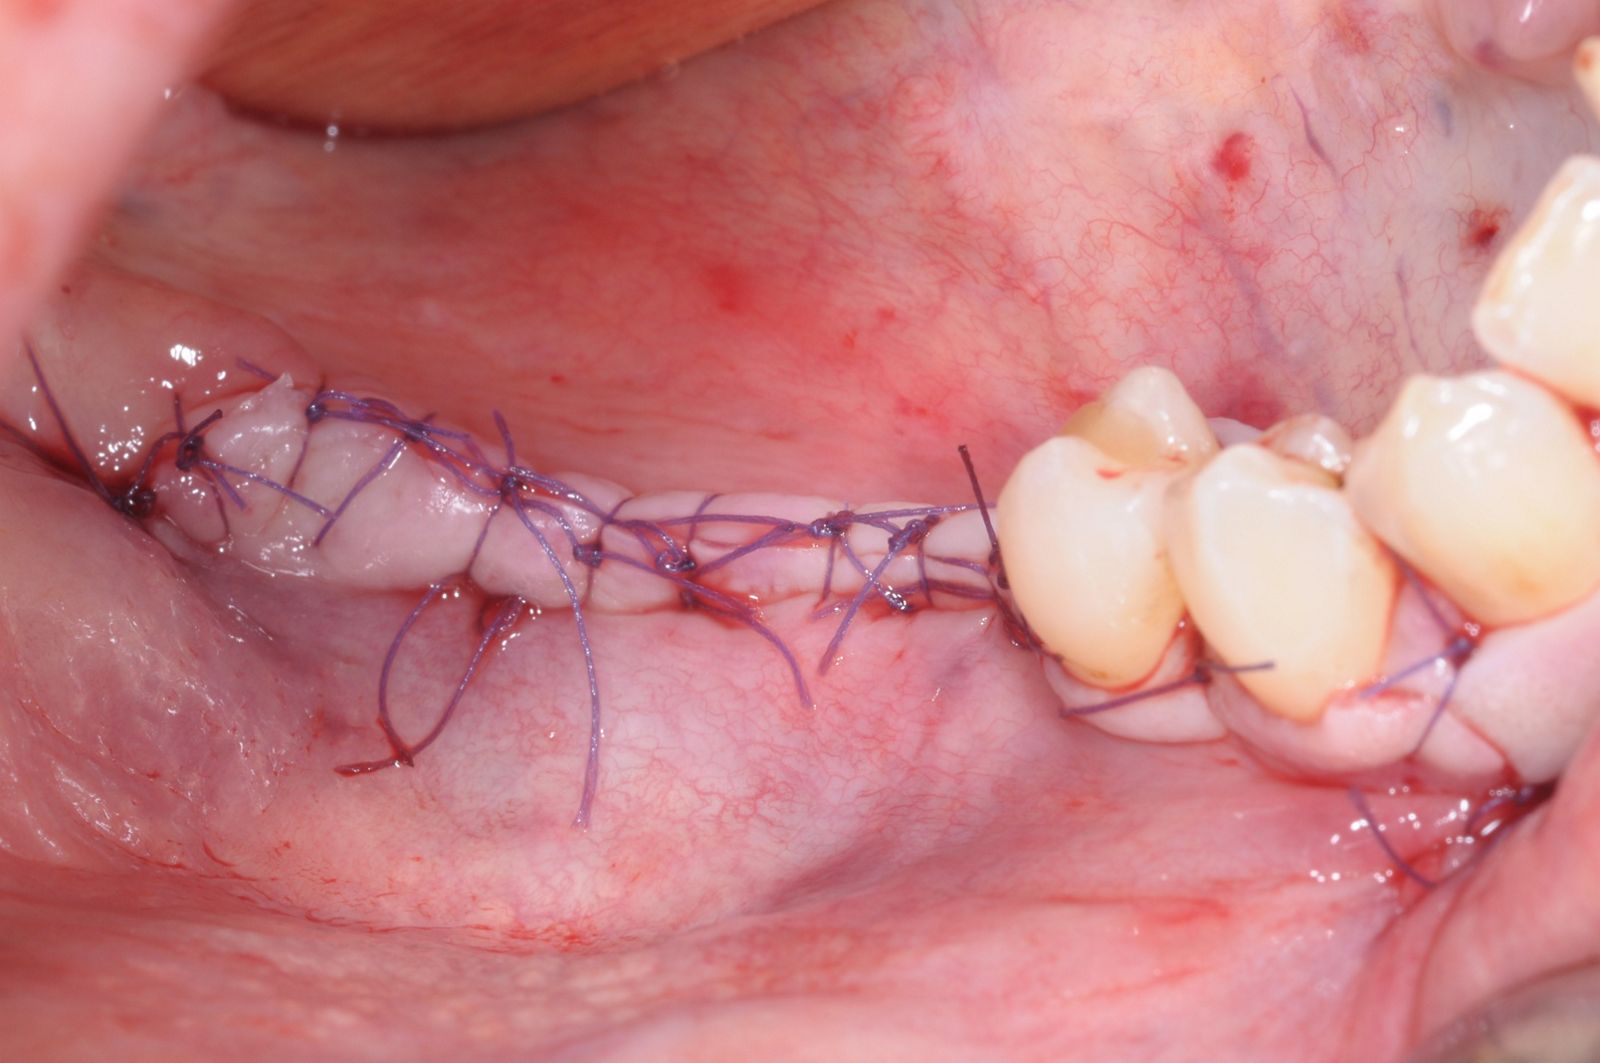

10/28 - Saliva-tight and compression-free wound closure with single-button and mattress suturesThree-dimensional augmentation with maxgraft® cortico - Dr. R. Würdinger